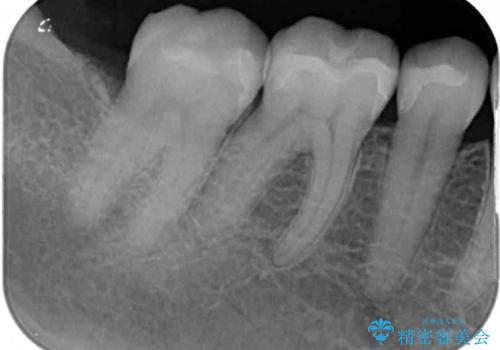

- 銀歯をセラミックにしたいとのことで来院された患者様です。

まず麻酔をして銀歯を外し、むし歯を除去し、形を整えて型取りします。

そして次の来院時、セラミックインレーを装着し、噛み合わせなどの調整を行います。

それを左右に分けて行いました。

インレーを装着するときは、唾液や血液による接着力の低下を避けるためにラバーダム防湿を行いました。